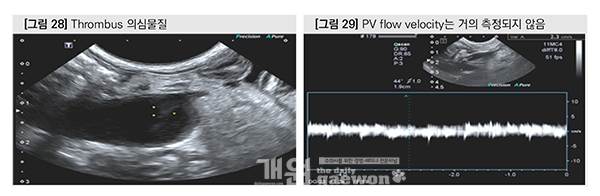

수술 4일째 portal v.에서 thrombus 의심 물질이 관찰되었고, PV의 blood flow는 측정되지 않았다. Splenic v.의 blood flow는 hepatofugal과 hepatopetal flow가 번갈아 가며 관찰 되었으나 gastroduodenal v.은 지속적으로 hepatofugal flow였다. Portal vein 내의 thrombus 형성과 함께 문맥 혈액은 splenic v.과 gastroduodenal v.으로 우회하고 있었다.

수술 10일째 portal vein flow velocity는 4cm/sec로서 다소 느리지만 normal flow가 측정되었다. Portal vein에서 thrombus는 관찰되지 않았고, splenic vein과 gastroduodenal vein의 flow는 지속적으로 portal vein 방향으로 흐르고 있었다.